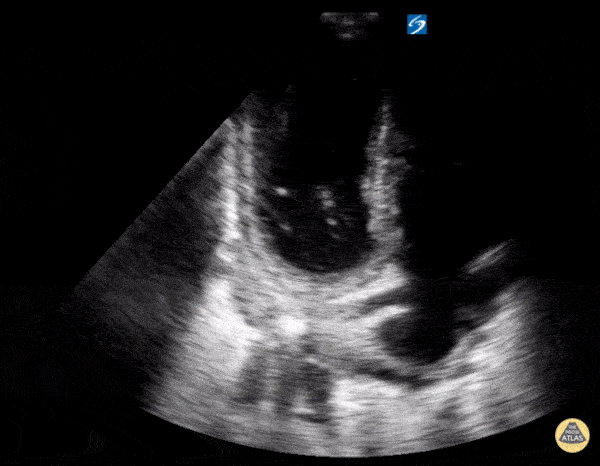

Left Ventricular Dysfunction - Apical Ballooning

A 50 years old, complaining of dyspnoea and chest pain. She had no prior history of cardiopulmonary disease. Initial ultrasound of the lung fields demonstrated plenty of B-lines bilaterally. An apical cardiac view (view is flipped with LV on left side of screen) demonstrates hypokinesis & aneurysmal dilation of the apex consistent with Takotsubo's cardiomyopathy. The patient's heart failure was managed supportively and a catheterization was performed during hospitalization that showed normal coronary artery stenosis. She had a full recovery Ilan Ben-Shabat 5th year medical student Aspiring emergency physician